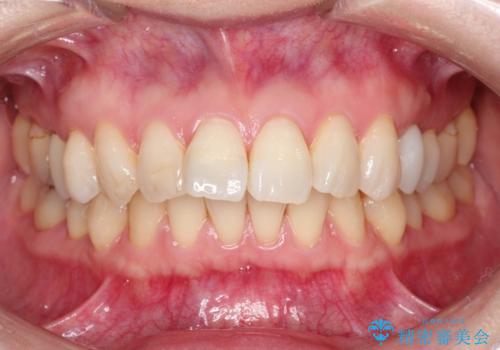

【インビザライン 】前歯を下げたい

- 前歯の凸凹と、前突を主訴に来院されました。

インビザライン にて治療を行なっております。

治療期間中はゴムかけを行なってもらうことで、前歯を下げることができました。